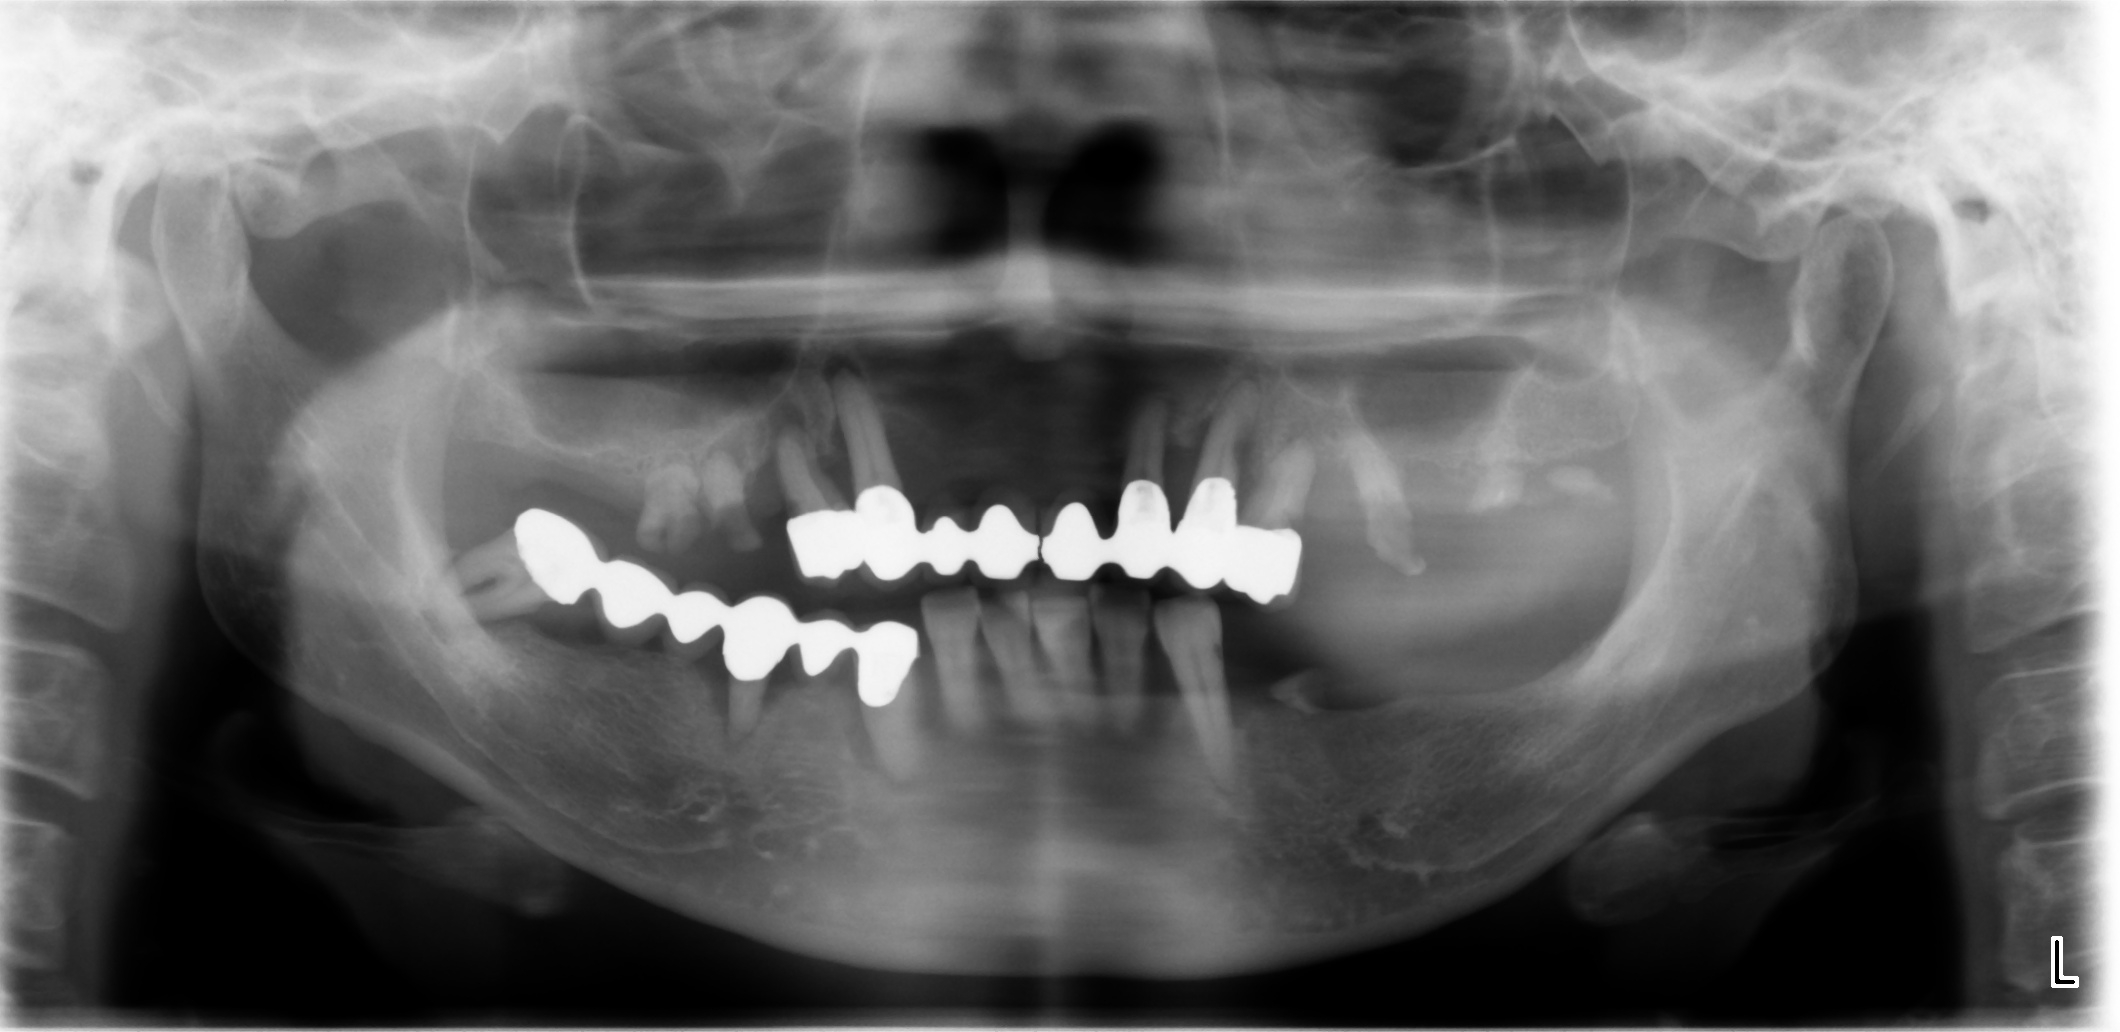

治療前(パノラマX線写真)

当院にて、歯周病治療で口腔内環境を整えた上でインプラント治療を行った結果、ご自身の歯のような見た目と噛み心地を回復。「人前で笑えるようになった」「食事が美味しい」と、健康な人と全く変わらない人生を取り戻されました。